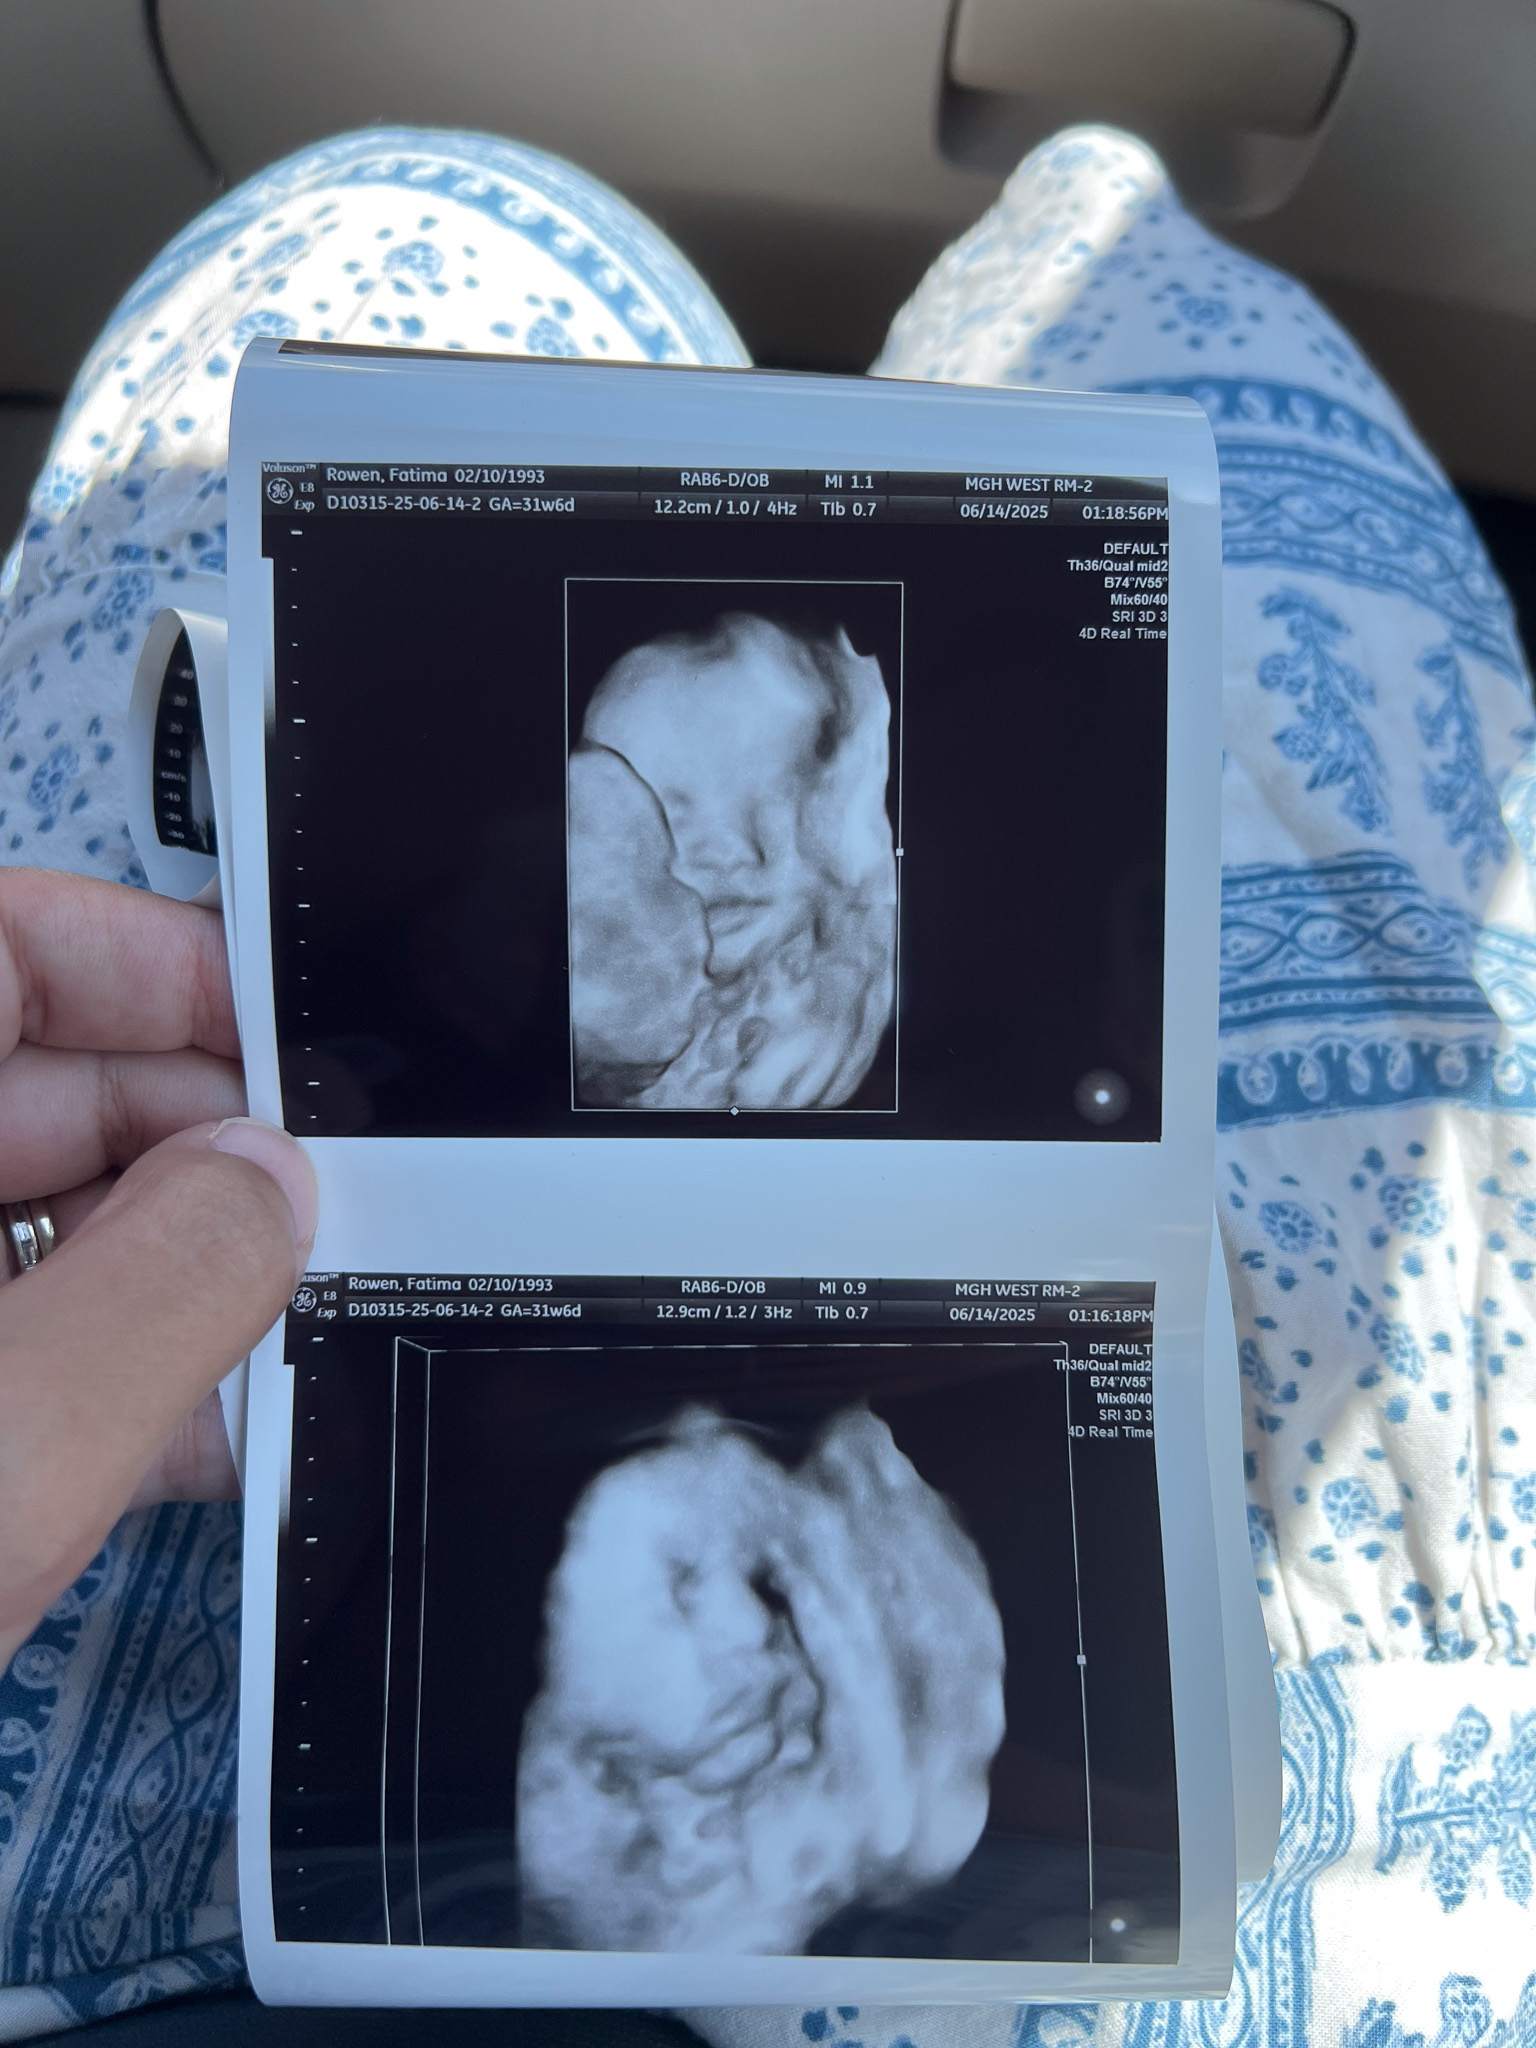

On June 14th, the last day of my 31-week pregnancy, Erik, Katya, and I went for a 3D/4D scan to peek at our baby boy’s face. This was one of the things I wanted to do when I was pregnant with Katya, but I never got around to it. This time, I was determined to experience it!

I booked the appointment just a few days in advance at First Peek 3D/4D Ultrasound (here), and I was able to get in easily. I was greeted by the ultrasound tech, and we immediately started the session. There was a little play section for toddlers to keep Katya occupied, so I could relax and enjoy the time looking at my son. During the session, the ultrasound lady kept telling me that he has lots of hair, and I was thinking, no wonder I have so much heartburn! She said he has hair on his head and also on his back.

I was able to see his chubby cheeks and cute lips. I saw him yawn and play with his foot by grabbing it. It’s so reassuring to see that he’s doing well inside me. It helps during those rough moments—like throwing up or dealing with heartburn—when I picture his cute face in my head. It helps me push through the sleepless nights. We also saw him moving around, which explains a lot of what I’ve been feeling in my belly.